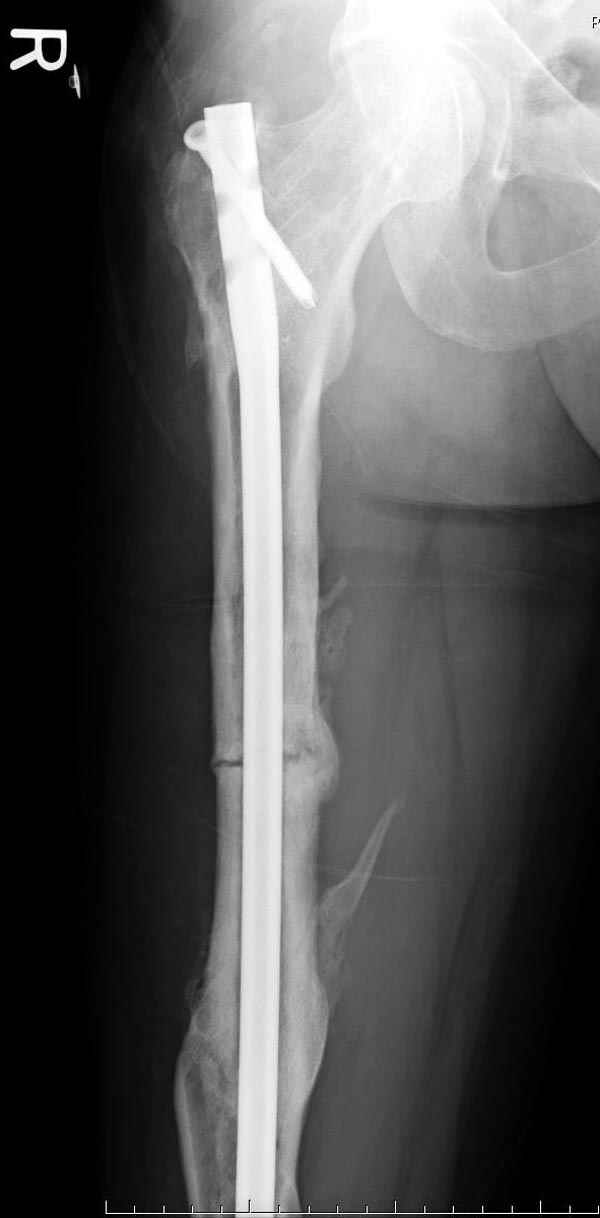

если первые 4 месяца послеоперационного периода проходил без проблем, но на 5 месяце появились боли в дистальном отделе бедра и температура, т.е. симптомы медуллярного инфицирования (рис №3, №4).

Замена реконструктивного штифта “Custom made Nail” с антибиотиком (рис №5, №6),

после промывки канала с рассверливанием внутреннего кортекса, через 4 недели антибиотический штифт удалили, оспалителный процесс остановлен и бедро сросся.